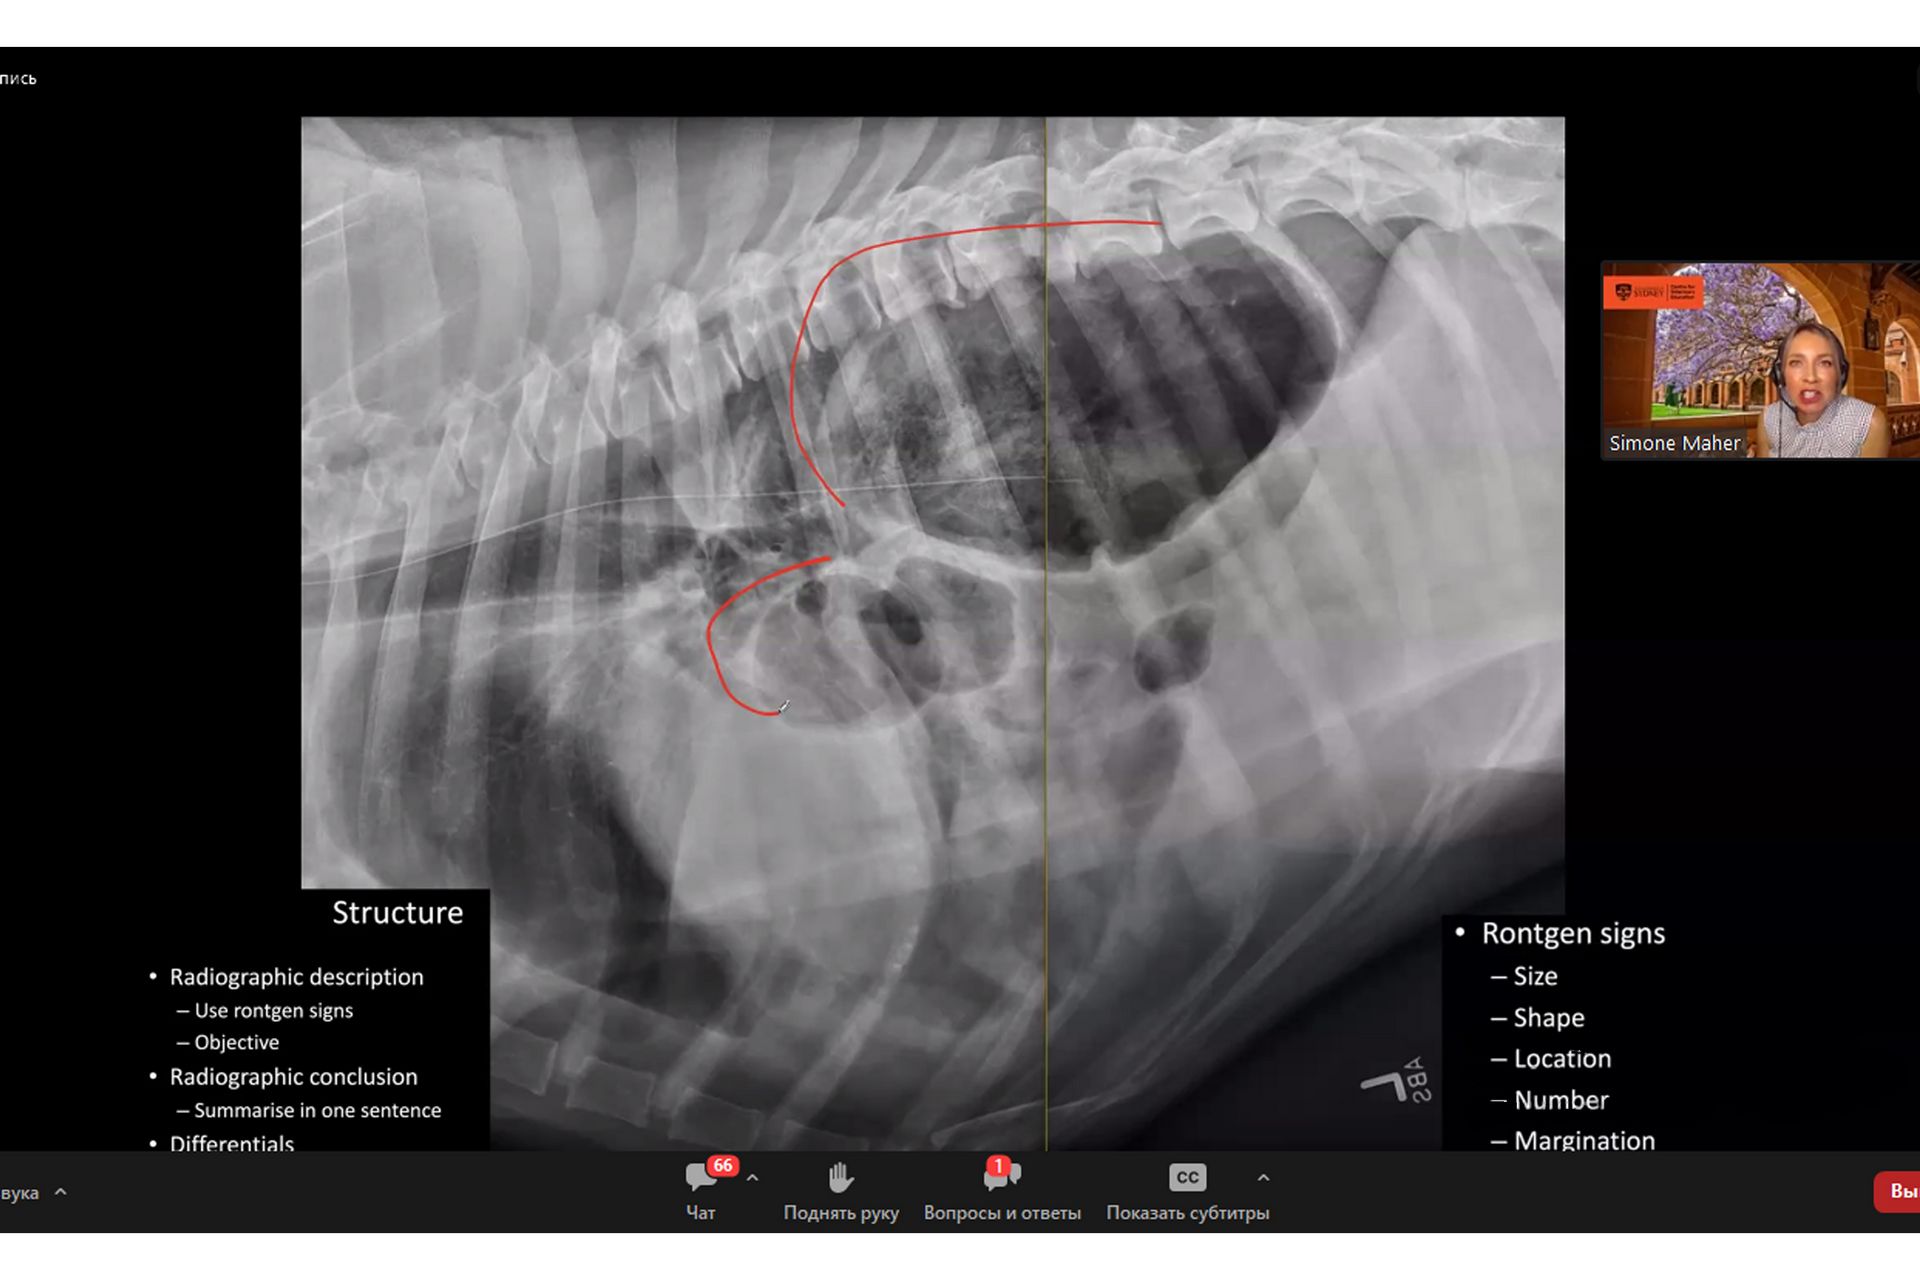

У заході прийняли участь науковці та  практикуючі лікарі ветеринарної медицини з усього світу. Спікером вебінару виступив Ксандер Хейзінг (DVM DipECVDI MRCVS), відомий сертифікований лікар із ветеринарної діагностичної візуалізації (DipECVDI) та клінічний радіолог, практикуючий спеціаліст з УЗД, рентгенографії, КТ, МРТ і флюороскопії. Доктор Хейзінг працював у реферальних та наукових колах в Австралії та Європі. Він є директором Остінської школи радіології тварин і надає послуги візуалізації ветеринарам Аделаїди та Південної Австралії.

Пан Ксандер провів майстер – клас з радіології та розповів про основні переваги даного методу дослідження, зокрема те, що сама процедура його проведення проста і не вимагає втручання в організм тварини і, в більшості випадків, не вимагає спеціальної підготовки і може бути виконана безпосередньо на прийомі у ветеринара для встановлення діагнозу, прогнозування перебігу захворювання, визначення його локалізації, спостереження динаміки результатів лікування.